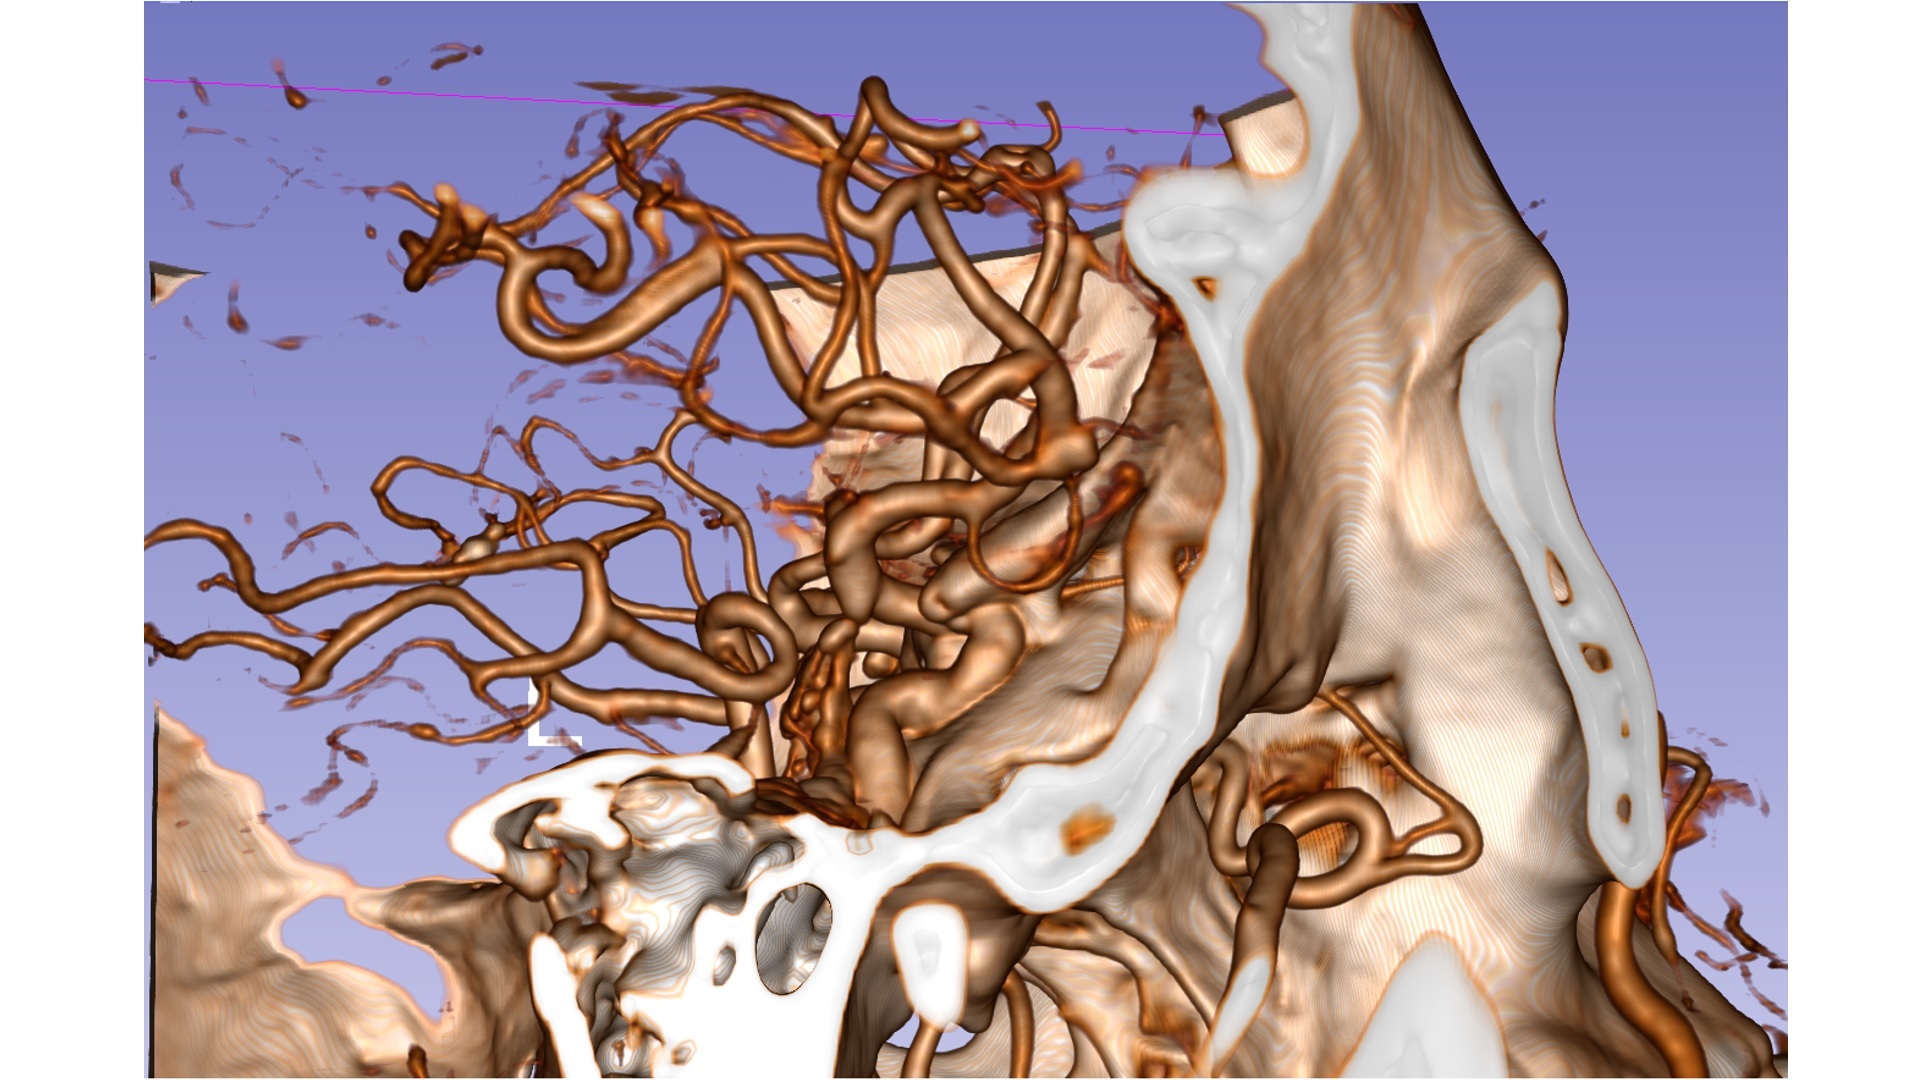

造影显示颅内多发动脉瘤:右侧大脑中动脉瘤;右侧A2-A3交界处动脉瘤;右侧后交通可疑动脉瘤。

右侧大脑中动脉瘤位于分叉部。

右侧A2/A3动脉瘤近端有一分支血管。